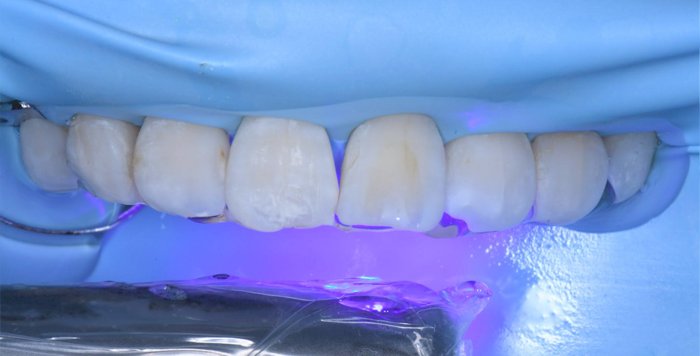

治療中の様子

修復した最後に、酸素で阻害された表面(Oxygen Inhibitation Layer)を最終重合しています。